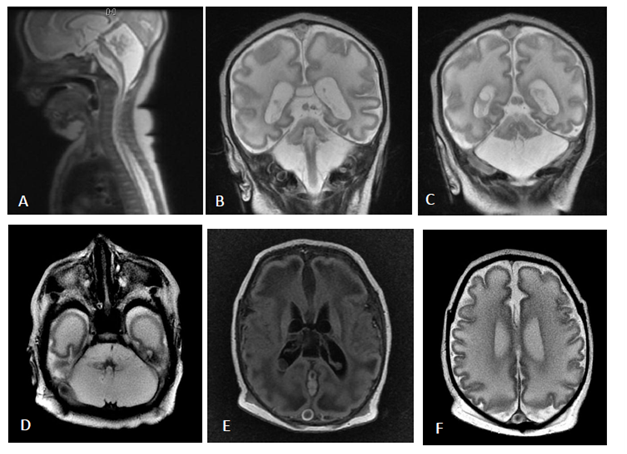

An MRI of the brain (Figure 1) showed features of poor gyration, as well as abnormal appearing white matter with a leukodystrophic appearance and profound pontocerebellar hypoplasia. An EEG was done which showed a burst suppression pattern (Figure 2); a diagnosis of Pontocerebellar hypoplasia type 1 (PCH type 1) was made and appropriate counseling provided to the parents. Genetic testing was not performed.

Figure 1 Sagittal (A), Coronal (B,C) and axial T2 MRI brain images shows profound ponto-cerebellar atrophy. Axial T1 (E) and T2 (F) show simplified gyral pattern and leukodystrophic white matter.